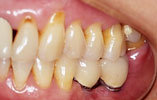

CASE3

下の奥歯2本が欠損 機能的回復

インプラント埋入前

インプラント埋入後

インプラントに

セラミッククラウンを装着

奥歯が2本失われ、従来は取り外し式の部分入れ歯を入れていました。2本のインプラントを埋入し、自分の歯と同様の感覚の「固定式」人工歯を入れ、噛む機能を回復しました。